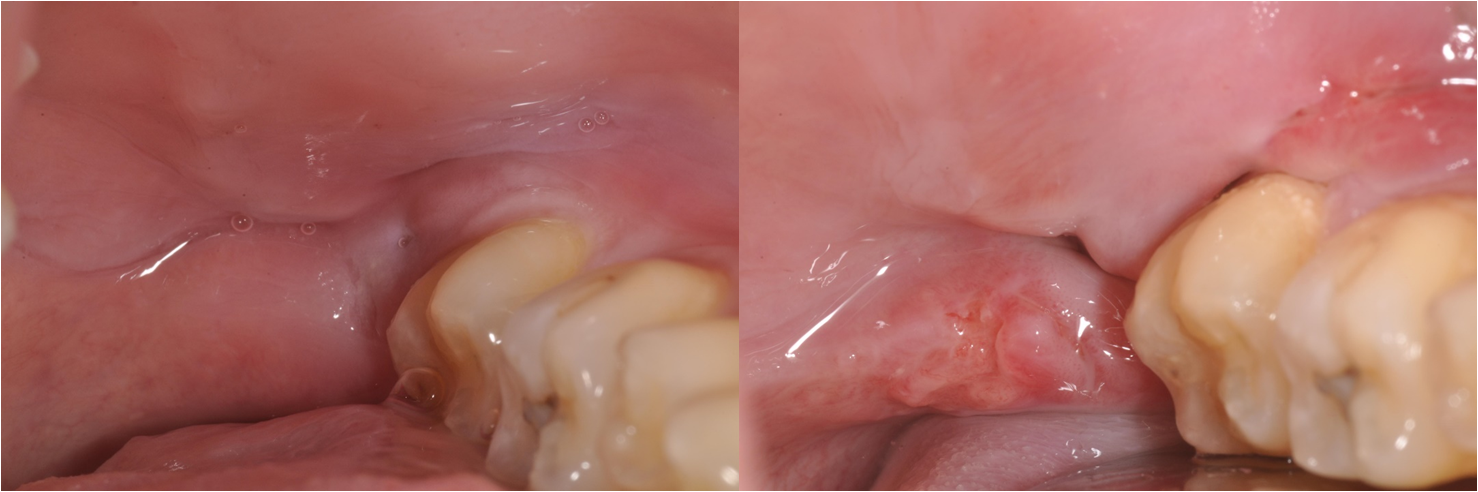

一週後傷口癒合理想

術前、術後比較